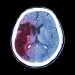

A stroke often occurs because of a narrowing or blockage in an artery that supplies blood to the brain. It can also happen because of a burst or leaking blood vessel in the brain. Blood pressure and fatty deposits (atherosclerosis) in the arteries are common causes of these problems. A stroke can occur in people of any age, but your chances of having a stroke increase as you get older.

In an ischemic stroke, your doctor will use drugs to dissolve the blood clot blocking blood flow to your brain. They’ll also give you medicine to prevent another clot from forming. They may also recommend a procedure called thrombolysis, in which they inject a drug into an artery in your arm to break up the clot.

In a hemorrhagic stroke, your doctor will treat the bleeding with surgery or other medical procedures. They’ll insert a thin tube (catheter) into an artery in your groin or wrist, then thread it to the blood vessels that carry blood to your head. Then they’ll release a dye and take X-rays to see where the clot is.